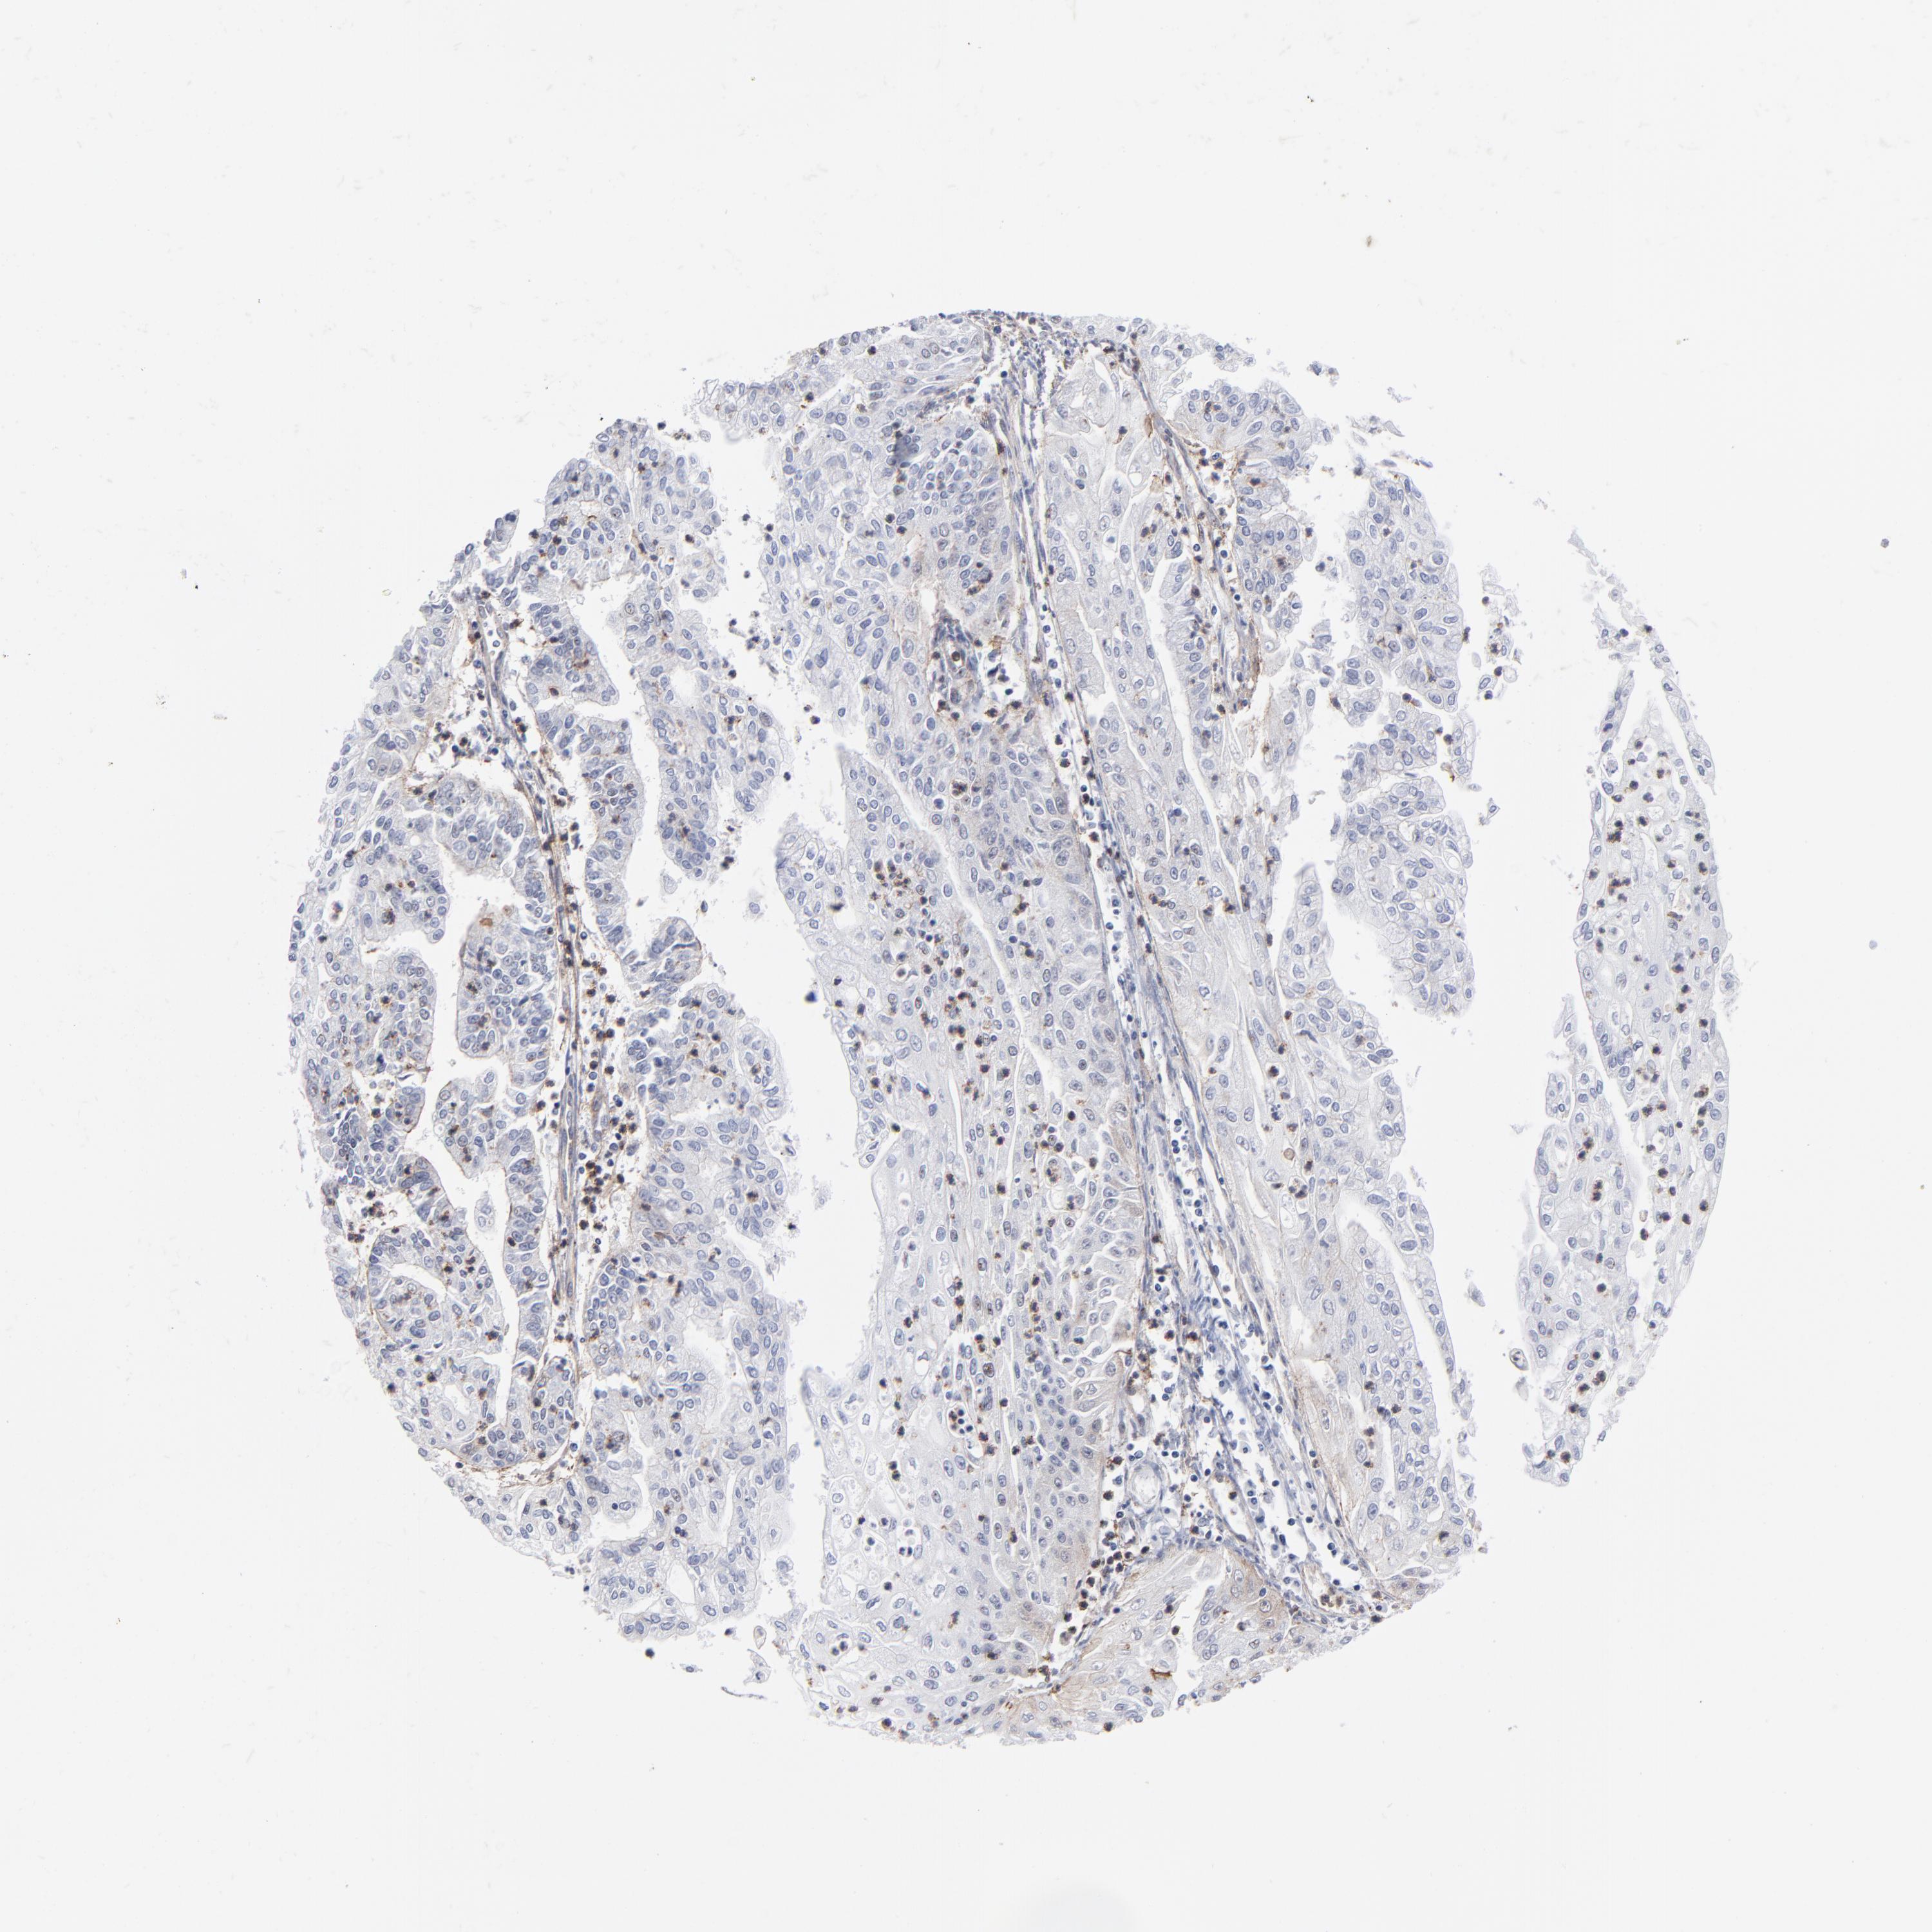

ENDOMETRIAL CANCER - Protein expressioni

A mouse-over function shows sample information and annotation data. Click on an image to view it in a full screen mode. Samples can be filtered based on level of antibody staining by selecting one or several of the following categories: high, medium, low and not detected. The assay and annotation is described here.

Note that samples used for immunohistochemistry by the Human Protein Atlas do not correspond to samples in the TCGA dataset.

Antibody stainingi

Antibody staining in the annotated cell types in the current human tissue is reported as not detected, low, medium, or high, based on conventional immunohistochemistry profiling in selected tissues. This score is based on the combination of the staining intensity and fraction of stained cells.

Each image is clickable and will lead to virtual microscopy that enables deeper exploration of all samples and also displays staining intensity scores, fraction scores and subcellular localization as well as patient and tissue information for each sample.

Antibody CAB003841

Staining

High

Medium

Low

Not detected

Intensity

Strong

Moderate

Weak

Negative

Quantity

>75%

75%-25%

<25%

None

Location

Nuclear

Cytoplasmic/membranous

Cytoplasmic/membranous,nuclear

Adenocarcinoma, NOS